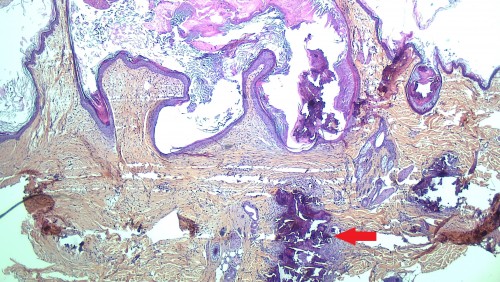

Figure 3 : Aspect histopathologique de la lésion le jour de la première consultation ; la flèche rouge montre les lésions minéralisées correspondant aux dépôts de calcium (calcinosis cutis) – Coloration HES, Grossissement X 40

Des raclages et une culture fongique sont réalisés et permettent d’exclure une démodécie et une dermatophytose. La cytologie (calques cutanés sur les collerettes épidermiques) révèle la présence de très nombreux polynucléaires neutrophiles majoritairement dégénérés, de nombreuses bactéries de type cocci en position extra et intracellulaire (phagocytose) et de rares macrophages confirmant l’hypothèse d’une pyodermite superficielle bactérienne (cf. figure 2), par ailleurs modérée sur le plan clinique. Un « crissement » a été ressenti lors de la cytoponction effectuée dans l’épaisseur de la plaque. Le prélèvement ainsi obtenu est paucicellulaire et montre de rares amas de matériel amorphe n’ayant pas capté la coloration, compatible avec un dépôt minéral. Une biopsie est réalisée et l’analyse histopathologique met en évidence des dépôts minéralisés, dermiques et épidermo-folliculaires (calcinosis cutis) et des plages de métaplasie osseuse (osteoma cutis) dermiques, en accord avec l’hypothèse clinique de calcinose cutanée (cf. figure 3). Le contrôle du traitement au trilostane et l’analyse des paramètres biochimiques ne montre aucune anomalie. L’utilité d’une IRM de l’encéphale est évoquée afin de tenter de faire la distinction entre un macro-adénome ou des micro-adénomes hypophysaires sécrétant de l’ACTH, et d’évaluer la faisabilité d’une éventuelle intervention chirurgicale (hypophysectomie). Cependant, cette dernière option est refusée par les propriétaires.